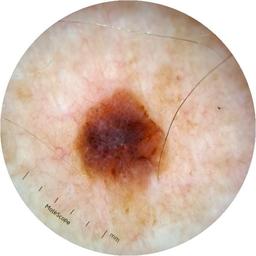

ISIC_6813604

MEL-SELF Trial, https://www.sydney.edu.au/medicine-health/our-research/research-centres/melself-project.html

acquisition_day 624

age_approx 75

anatom_site_1 Head and neck

anatom_site_general head/neck

diagnosis_1 Benign

diagnosis_confirm_type single image expert consensus

fitzpatrick_skin_type I

image_type dermoscopic

personal_hx_mm True

sex male